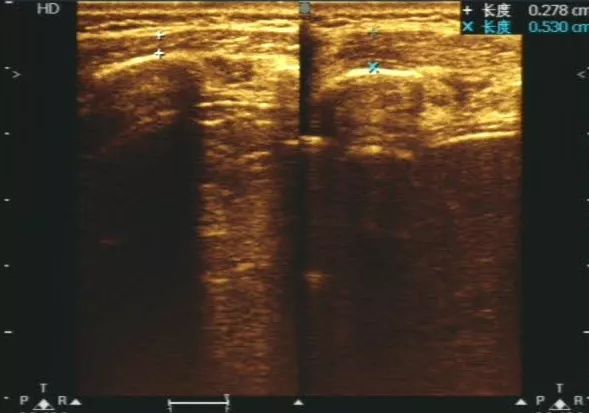

44岁女性患者,右膝关节疼痛,放射检查未见骨关节异常,后来经过肌骨超声检查提示考虑右侧膝关节内侧副韧带挫伤,肌骨超声看到你不知道的肌肉损伤。